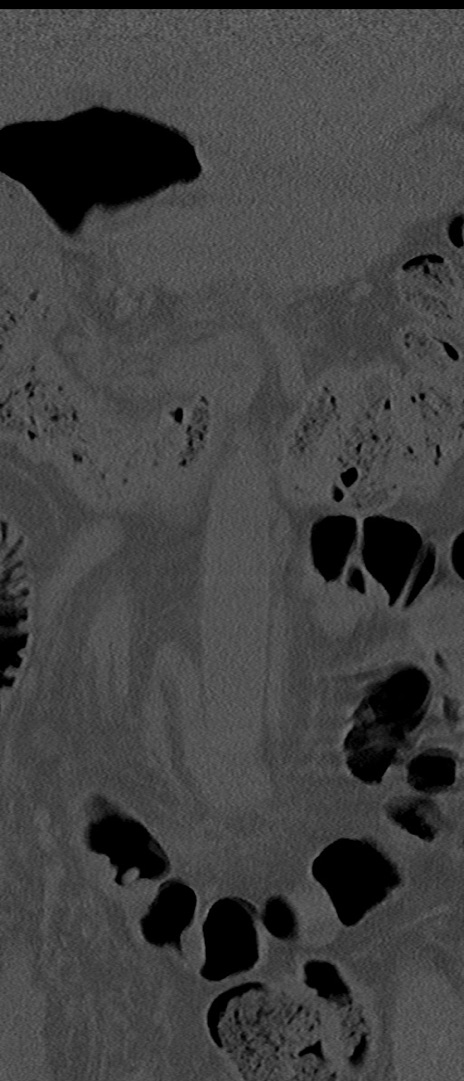

腰椎CT

横断像